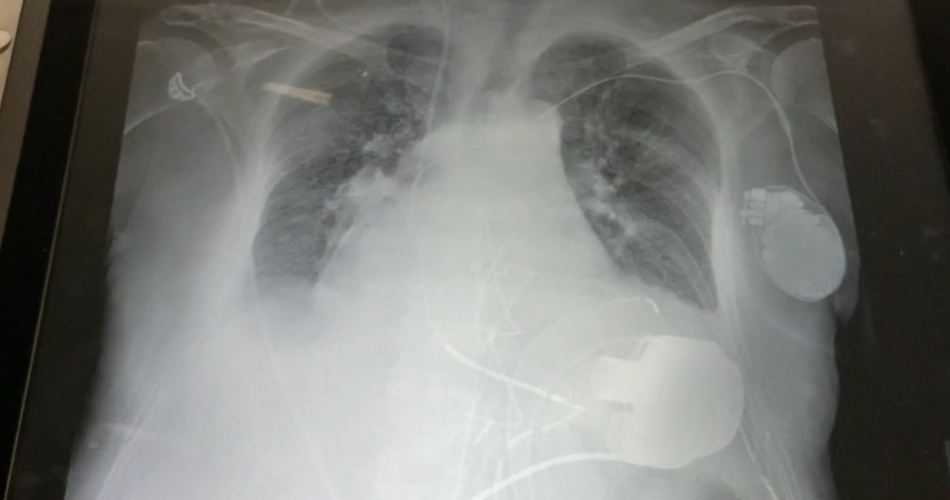

Il dispositivo di assistenza ventricolare (LVAD) preleva il sangue dal ventricolo sinistro e lo pompa ossigenato nell’aorta, utilizzando il nuovo sistema a levitazione magnetica impiantato per la prima volta in Puglia.

La pompa del dispositivo di assistenza meccanica al circolo, infatti, viene impiantata all’interno del corpo mediante l’intervento cardiochirurgico, è alimentata da batterie collegate a un piccolo controller esterno attraverso un cavo che fuoriesce dall’addome del paziente.